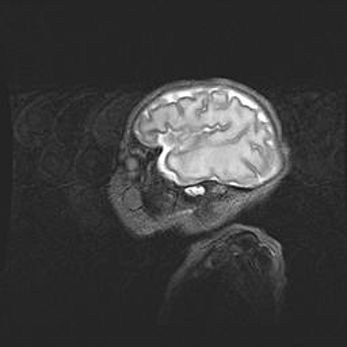

Наружная гидроцефалия с возможной атрофией височных областей.

Возраст: 28 дней

Вес: 3670 г

Пол: мужской

Окружность головы: 38 см

Срок гестации: 40 недель

Гидроцефалия головного мозга у новорожденных – это заболевание, которое характеризуется скоплением избыточного количества спинномозговой жидкости в желудочковой системе головного мозга в результате затруднения её перемещения от места выработки к месту поглощения в кровеносную систему или вследствие нарушения абсорбции. При открытой наружной форме гидроцефалии у новорожденных расширяются и переполняются субарахноидные пространства.

При нормотензивных  формах,  которые,  как  правило,  являются  следствием  перенесенных ишемических  повреждений  паренхимы  мозга,  возможно  сочетание микроцефалии  с нормотензивной гидроцефалией. В основе данных изменений лежит атрофия больших полушарий с преимущественной  локализацией  в  лобно-височных  областях.